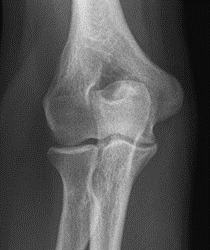

Które zdjęcie RTG stawu łokciowego zostało wykonane w projekcji skośnej w rotacji zewnętrznej?

A. Zdjęcie 1

B. Zdjęcie 2

C. Zdjęcie 3

D. Zdjęcie 4